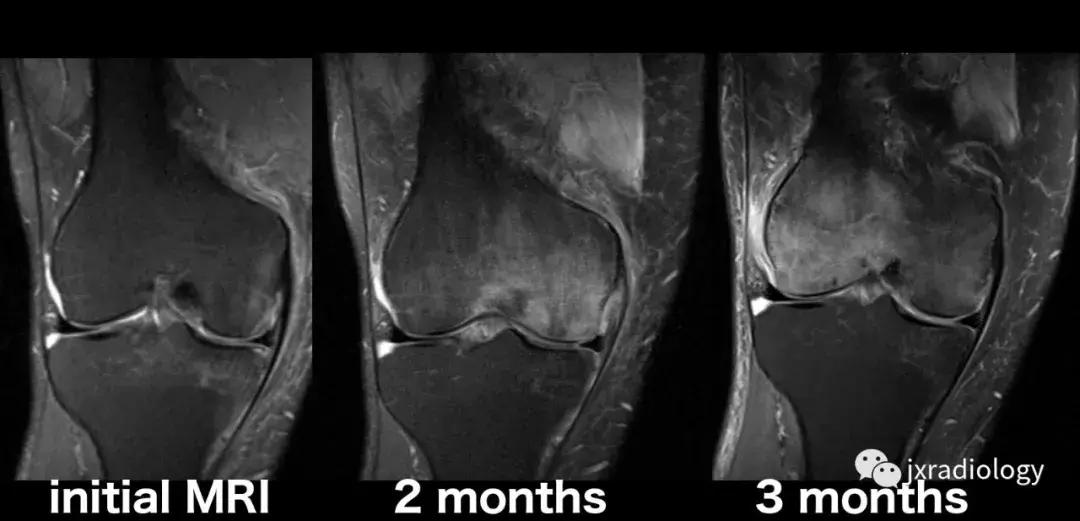

图26:局限性游走性骨质疏松症(具有位置变化的短暂性骨髓水肿综合征)(连续冠状PD-FS-WI):在一些情况下,在连续MRI上看到骨髓水肿的位置变化,这被称为局限性游走性骨质疏松症(RMO);尽管可以自愈的短暂性骨髓水肿综合征的情况更为常见,但可以在一小部分病例中转移到不同的关节,或者(甚至更罕见)转移到同一关节内的不同部位(关节内转移) ,如关于该患者所见。在这个关节内RMO病例中,没有创伤史,水肿始于股骨内侧髁,3个月后发现转移到外侧髁。